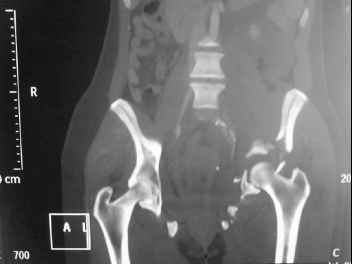

I'm posting this case on behalf of Dr. Pedro Caba, he is unable to post but able to read. 41 yo female , fall from 10 meters five days ago. Hemodynamically unstable on admission treated by angio and embolization and skeletal traction, with no external support. No associated injuries. Based on CT scan the pt has a both column fracture with conminuted dome and displaced anterior column and a sacral Denis 1 fracture with a displaced left ala. I think the best approach for the acetabular fracture is ilioinguinal with Smith-Petersen extension but don't know exactly the sequence . Will you start with the sacral fracture? Which technique? Thanks in advance Pedro Caba Unidad de Trauma Hospital 12 de Octubre Madrid Spain

This complex and displaced sacral injury is likely an H pattern...2 hemipelvic components, an upper sacral component which remains attached to the lumbar spine, and a caudal sacral component...there are typically anterior ring injuries as well...in this patient's example, the left sided acetabulum also has been exploded.

Most H pattern sacral fractures have the transverse fracture limb of the "H" at the upper-second sacral segment junction or disc region...some fracture thru the second segment, and some or at other sites...but most yield thru the upper-second sacral segments junction...with variable traumatic associated neurological findings.

The hemipelvic components' displacements depend on their instability...this patient's left side seems to be the worst.

The transverse fracture limb liberates the upper sacral segment and its attached lumbar-thoracic-cervical spine to displace...usually anteriorly and in kyphosis.